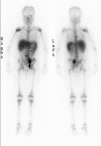

Fig. 2. Gammagrafía con Ga67: depósitos de captación patológicos supra e infradiafragmáticos. Afectación de cadenas ganglionares mediastínica derecha, paraaórtica derecha e ilíaca izquierda.